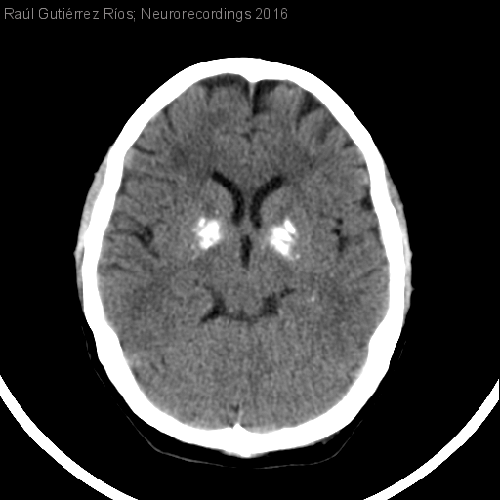

Diagnóstico final: Enfermedad de Fahr esporádica

Mujer de 47 años de edad, sin antecedentes personales ni familiares de interés, remitida por su médico de familia por cefalea. Aquejaba trastorno afectivo, insomnio mixto y cefalea de perfil tensional desde hacía un año. La...